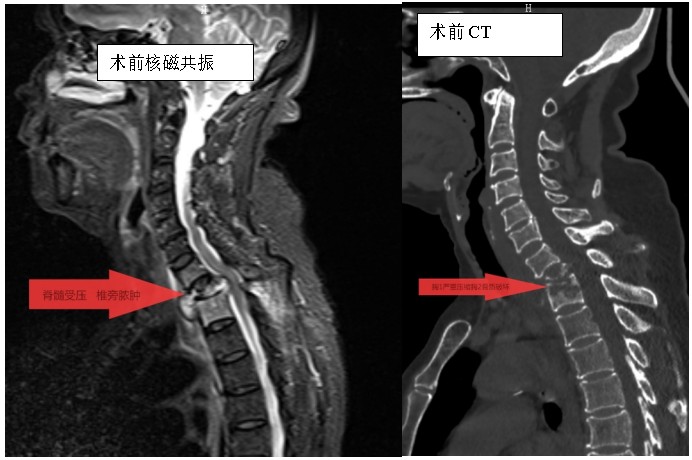

家住耒陽(yáng)的70歲的李奶奶,因“頸胸背部疼痛不適伴雙上肢麻木6個(gè)月”,來(lái)到衡陽(yáng)市中心醫(yī)院脊柱外科住院,住院當(dāng)天,患者頸胸椎核磁共振顯示:胸1、2椎體骨質(zhì)破壞,伴胸1、2椎旁軟組織腫脹、同層面椎管變窄,因脊髓受壓而導(dǎo)致頸胸背部疼痛。在錢軍博士帶領(lǐng)下,醫(yī)療團(tuán)隊(duì)詳細(xì)予以完善相關(guān)檢查后,研究患者的臨床資料,考慮脊柱結(jié)核并椎旁膿腫的可能性大,由于患者胸1椎體病理性骨折并椎管狹窄,遂囑患者嚴(yán)格臥床休息,術(shù)前給予標(biāo)準(zhǔn)四聯(lián)抗結(jié)核藥物治療2周,以控制活動(dòng)性結(jié)核感染,降低術(shù)中播散風(fēng)險(xiǎn),并嚴(yán)密監(jiān)測(cè)肝腎功能及血常規(guī)情況。